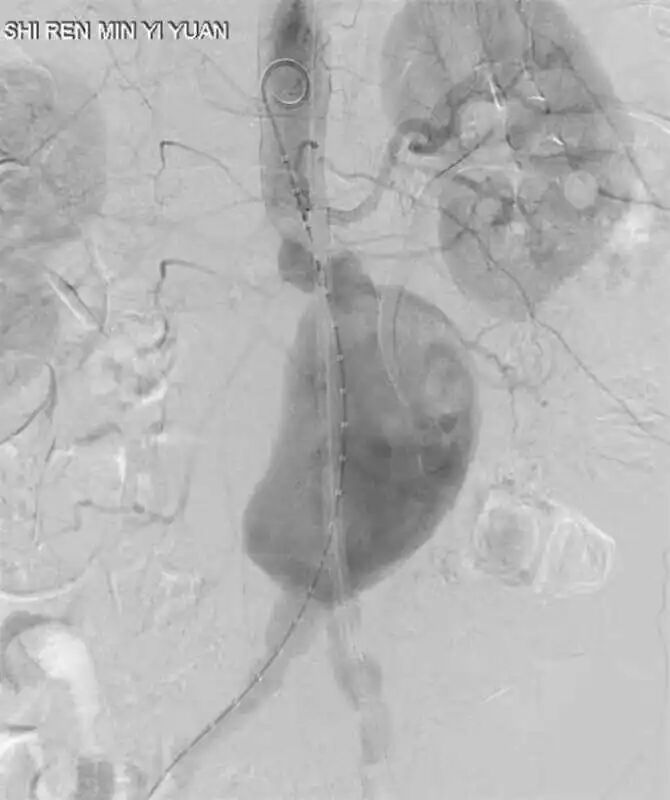

术后影像

介入血管外科团队凭借精湛的技术,在专用DSA机器的引导下,他们如同在微观世界里进行一场精密的“导航”。支架放置的精准度是手术成功的关键。放置过高可能阻塞肾动脉血供,过低则可能影响远端血流。经过精心操作,手术团队成功将覆膜支架定位于理想位置,完全隔绝了动脉瘤,同时保证了重要分支血管的血流通畅。最终,顺利拆除了患者体内的“不定时炸弹”,这场高难度手术最终圆满成功!